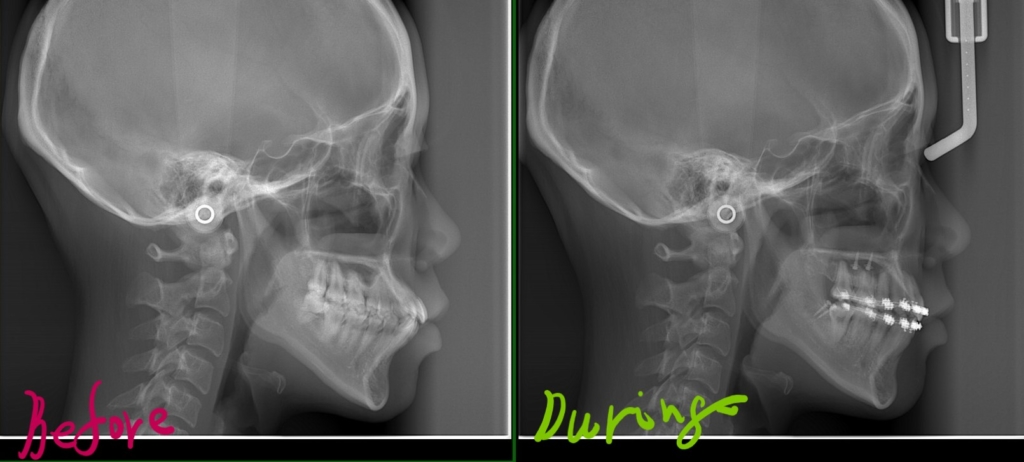

【途中経過】

抜歯スペース分をすべて使い、歯並びをきれいにして、前歯を最大限に後方へ引っ込ませました。 現時点でココまで変化しました。

矯正を始める前の時点と治療途中の時点をレントゲン写真で比較してみると、

残念ですが、口元はあまり明確な変化は見られません

最初の時点と比べて、口元も少しは引っ込んだように見えますが、変化はそこまでありません。

その理由は、、、

先ず、歯並びの乱れをキレイにすることに抜歯スペースを使い、余ったスペース分だけ前歯を引っ込める、というように治療を進めて行かざるを得ません。 そうなるとどうしても前歯を後方(奥)へ引っ込める量、ひいては口元の変化量が減ってしまうのです。

そこで今回は、もう少し引っ込ませたい分をアンカースクリューを併用して歯列を丸ごと後方へ移動させ(引っ込ませて)、口元をもっとスッキリと変化させよう!という治療プランを実行することにしました。

その変化をレントゲン写真で追ってみましょう。